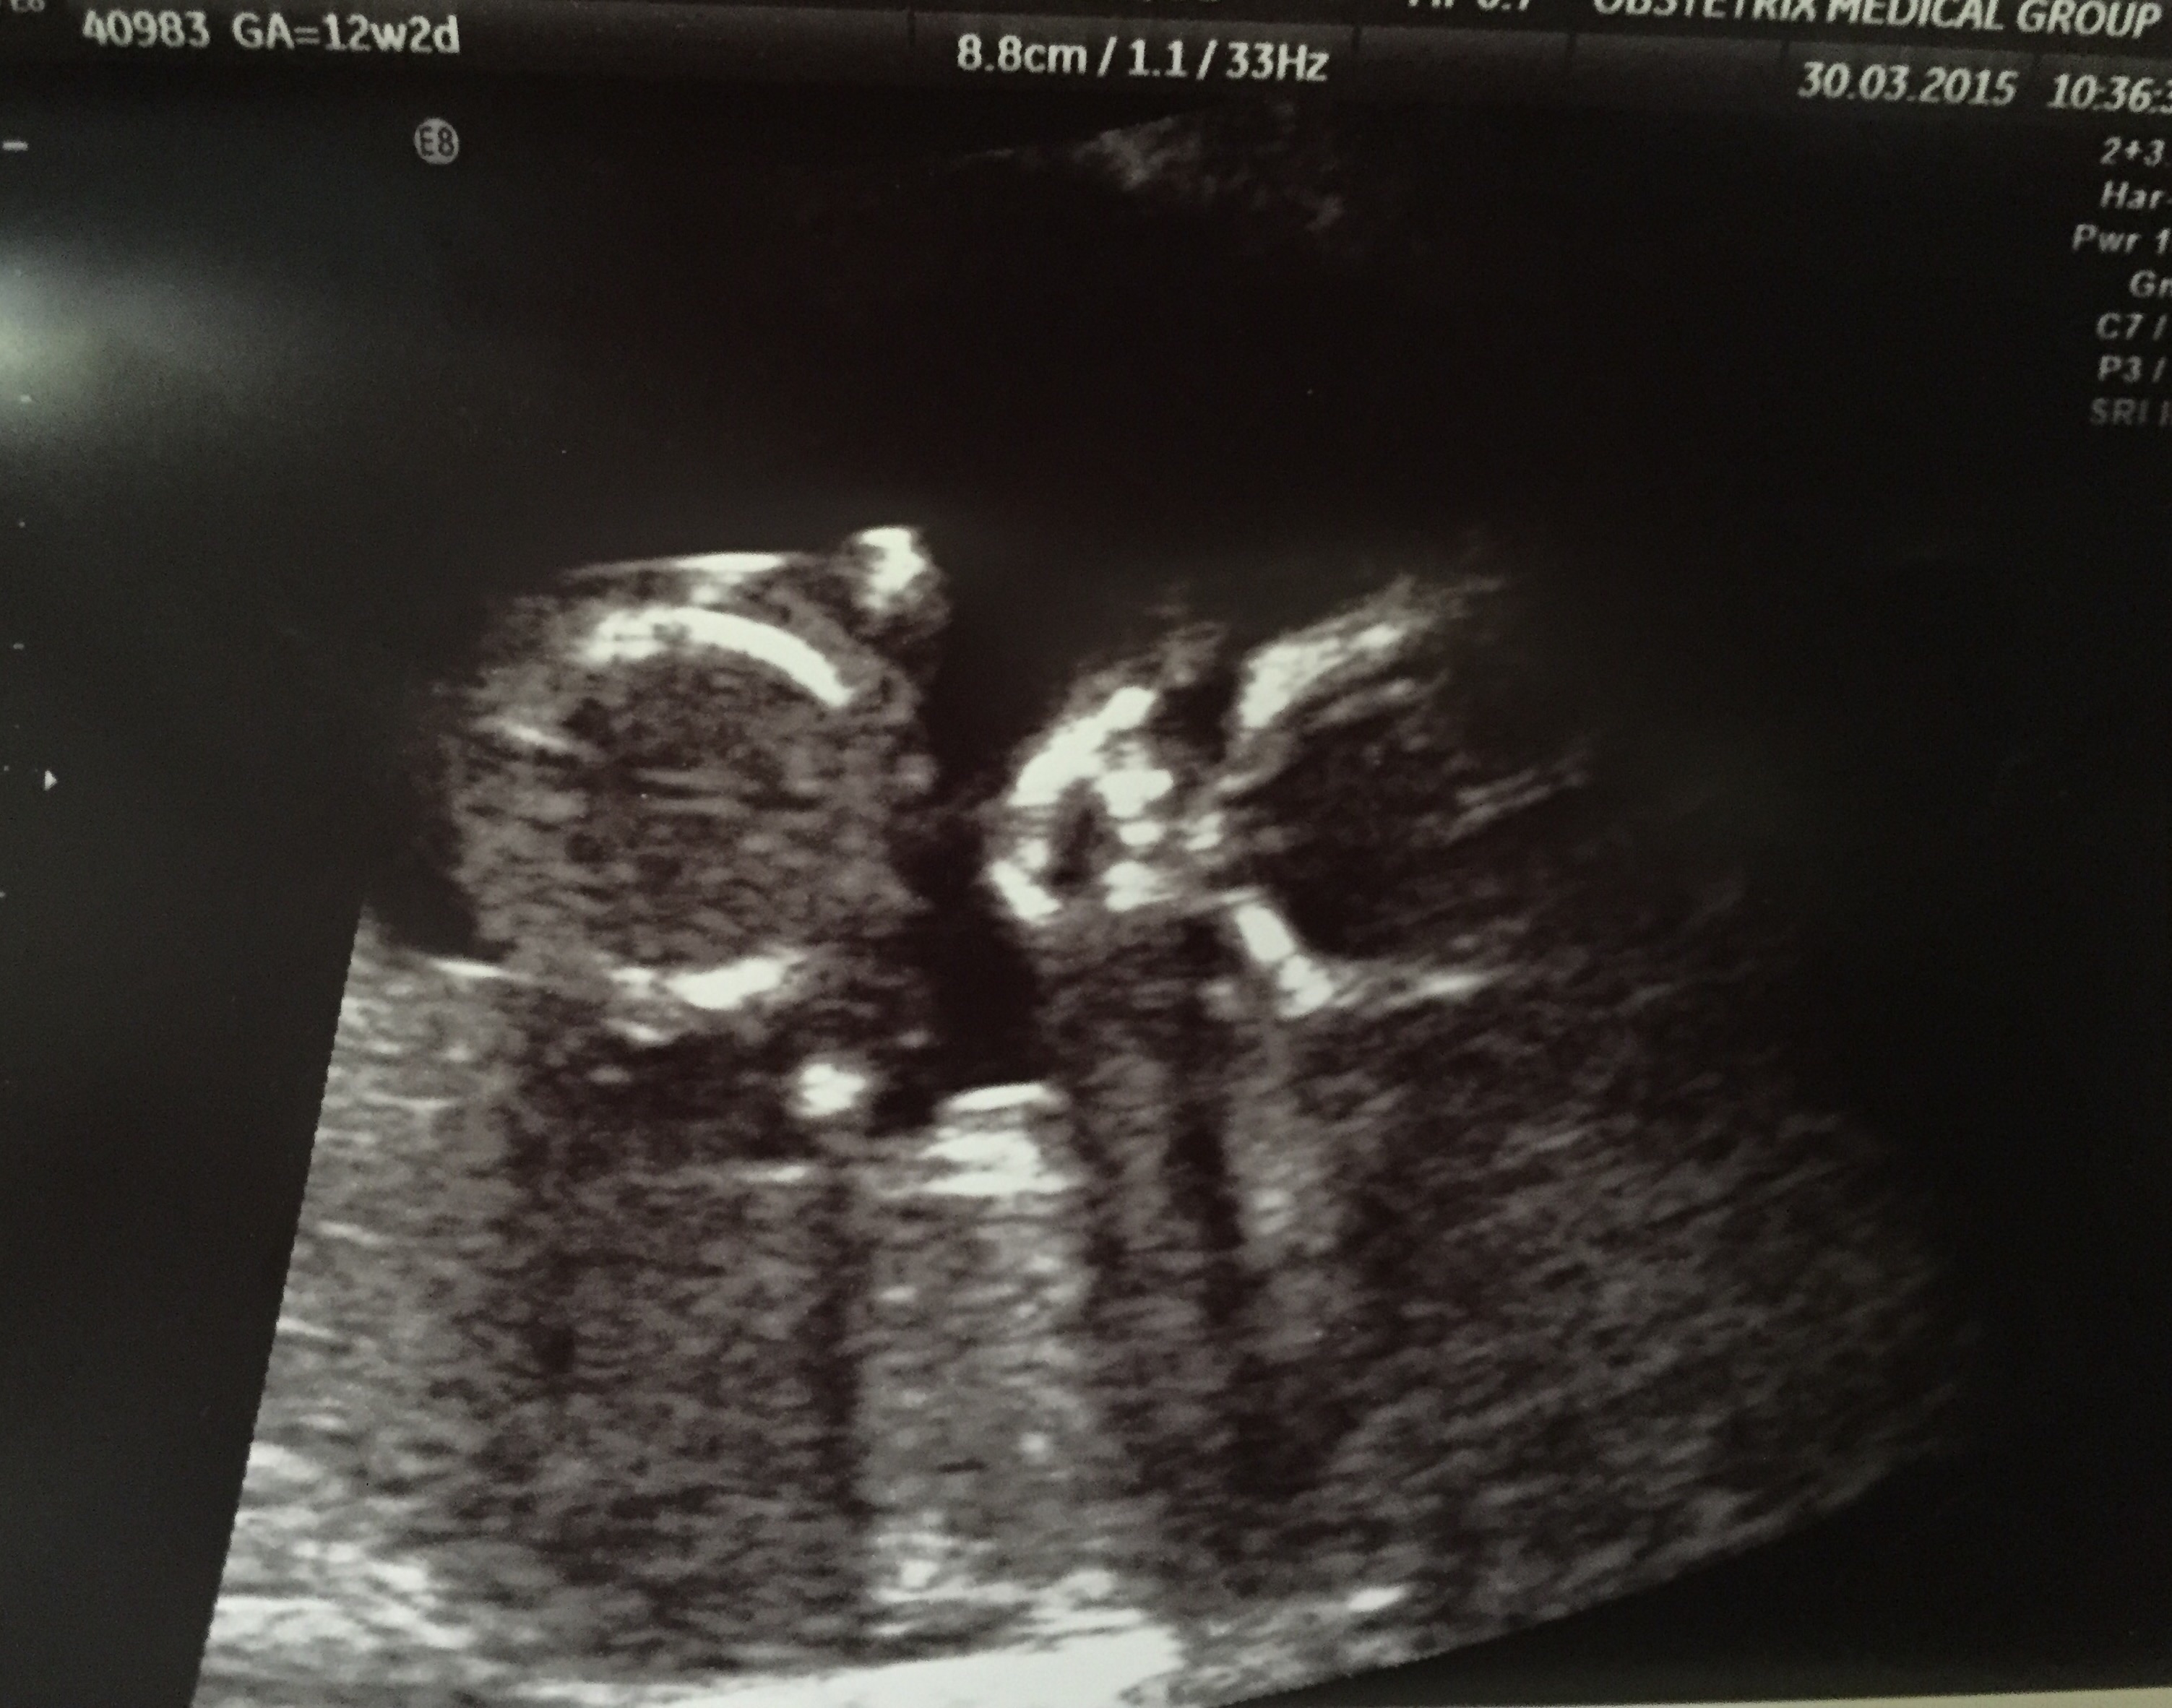

Here's our little love at 12 weeks! I can't get over how much he/she already looks like a 'real' person, can't wait for the next US when we find out the sex! So excited

We also graduated up one whole day! 12w 1d today.

12 week ultrasound